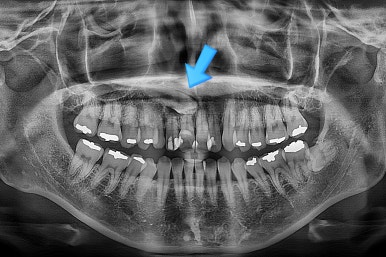

초진 시 X-ray를 보면 큰 문제가 있구나 바로 알아차리실 수 있을건데요.

화살표 부분이 송곳니 입니다.

송곳니가 제 위치로 나오지 못하고 주위 치아들 방향으로 누워있는 상태로 매복되어 있는데요.

그러면 송곳니 자리에 있는 치아는 뭐냐?

바로 진작에 빠졌어야 할 유치가 남아서 자리를 대체하고 있었죠.